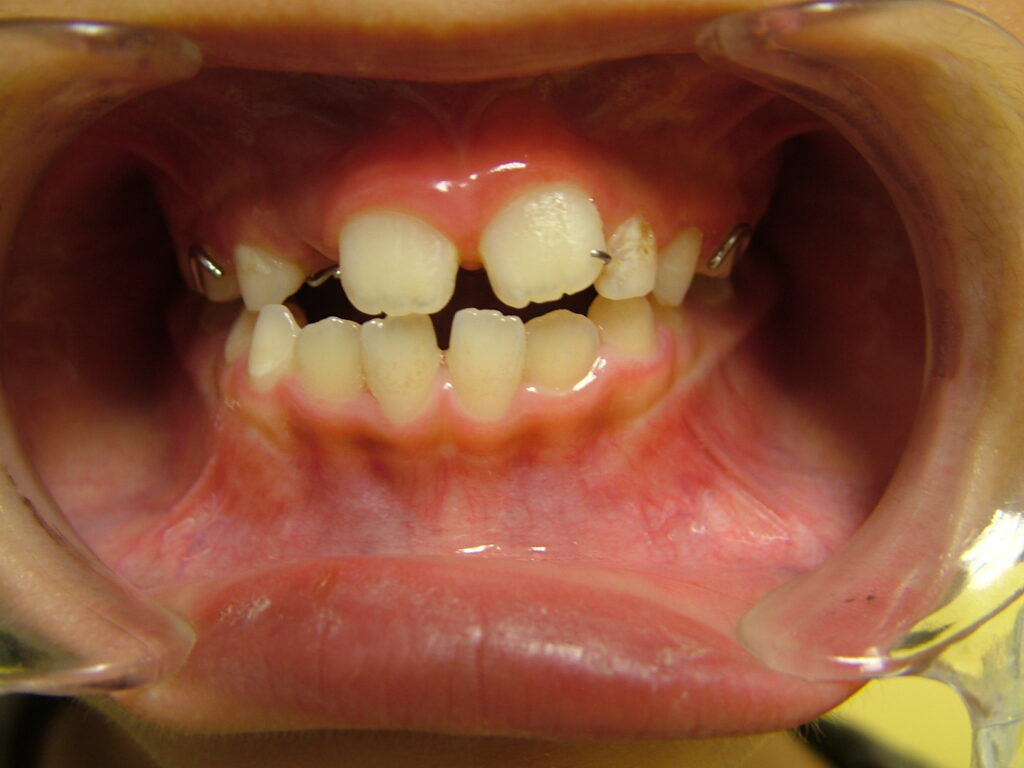

治療前

- 初診:2014年、8歳男児、

- 主訴:上の歯の隙間と歯の傾きが気になる。

- 診断:1級咬合、左偏位、下永久歯(犬歯)萌出スペース不足